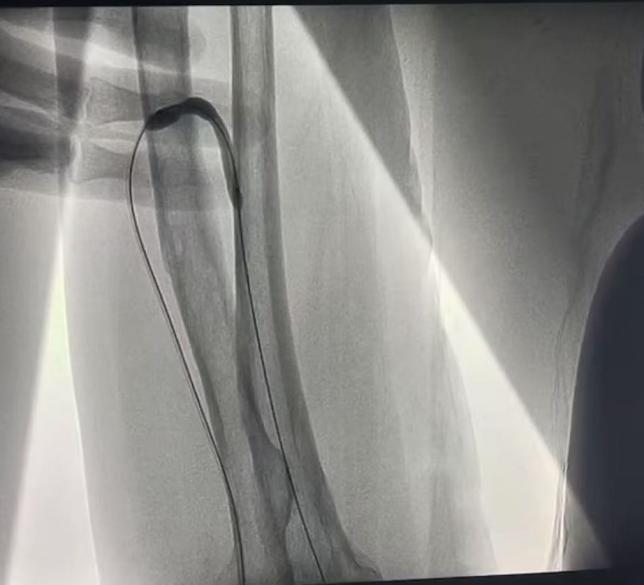

近日,在介入科大力协作和上级医院专家指导下,我院肾内科成功开展首例DSA引导下动静脉内瘘球囊扩张术(PTA under DSA guidance),顺利为透析患者打通“生命线”。

现年72岁的陆奶奶是外院一位靠血液透析维持生命的尿毒症患者,日前因左前臂人工内瘘功能不良再次前来我院就诊。入院后经查发现患者内瘘吻合口明显狭窄,进而导致内瘘功能不良,不能透析使用。患者高龄,为了保护和充分利用患者宝贵的血管资源,科室透析通路团队经过充分评估,决定对陆奶奶进行DSA引导下动静脉内瘘球囊扩张术。

经过充分沟通同意和术前积极准备,近日,在介入科协作和上级医院专家指导下,顺利经皮下穿刺患者动静脉内瘘,然后在DSA引导下将球囊送入血管的狭窄部分进行扩张。手术过程顺利,患者伤口小,痛苦轻,出血少。术后患者内瘘处听诊血管杂音清晰,可触及明显震颤,远心端血管充盈显著,超声评估内瘘吻合口血流量达标,手术十分成功。经过悉心指导进行内瘘功能锻炼和保护后,患者已于日前满意出院,回当地继续透析,同时科室密切随访。